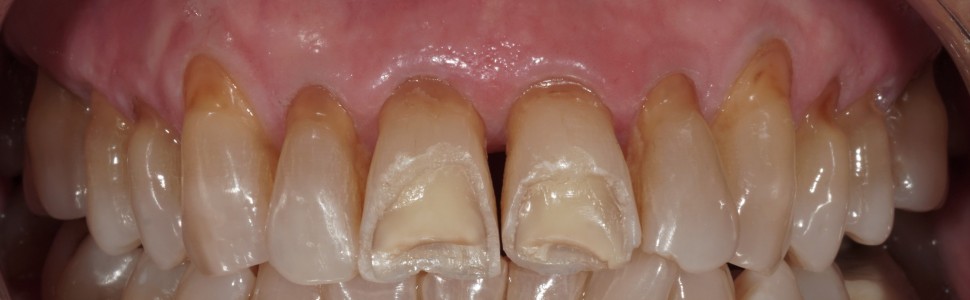

Ryc. 1. Stan przed leczeniem po złożonym złamaniu żuchwy – dyskluzja po lewej stronie.

Ryc. 2. Stan kliniczny podczas pierwszej wizyty wgabinecie stomatologicznym.